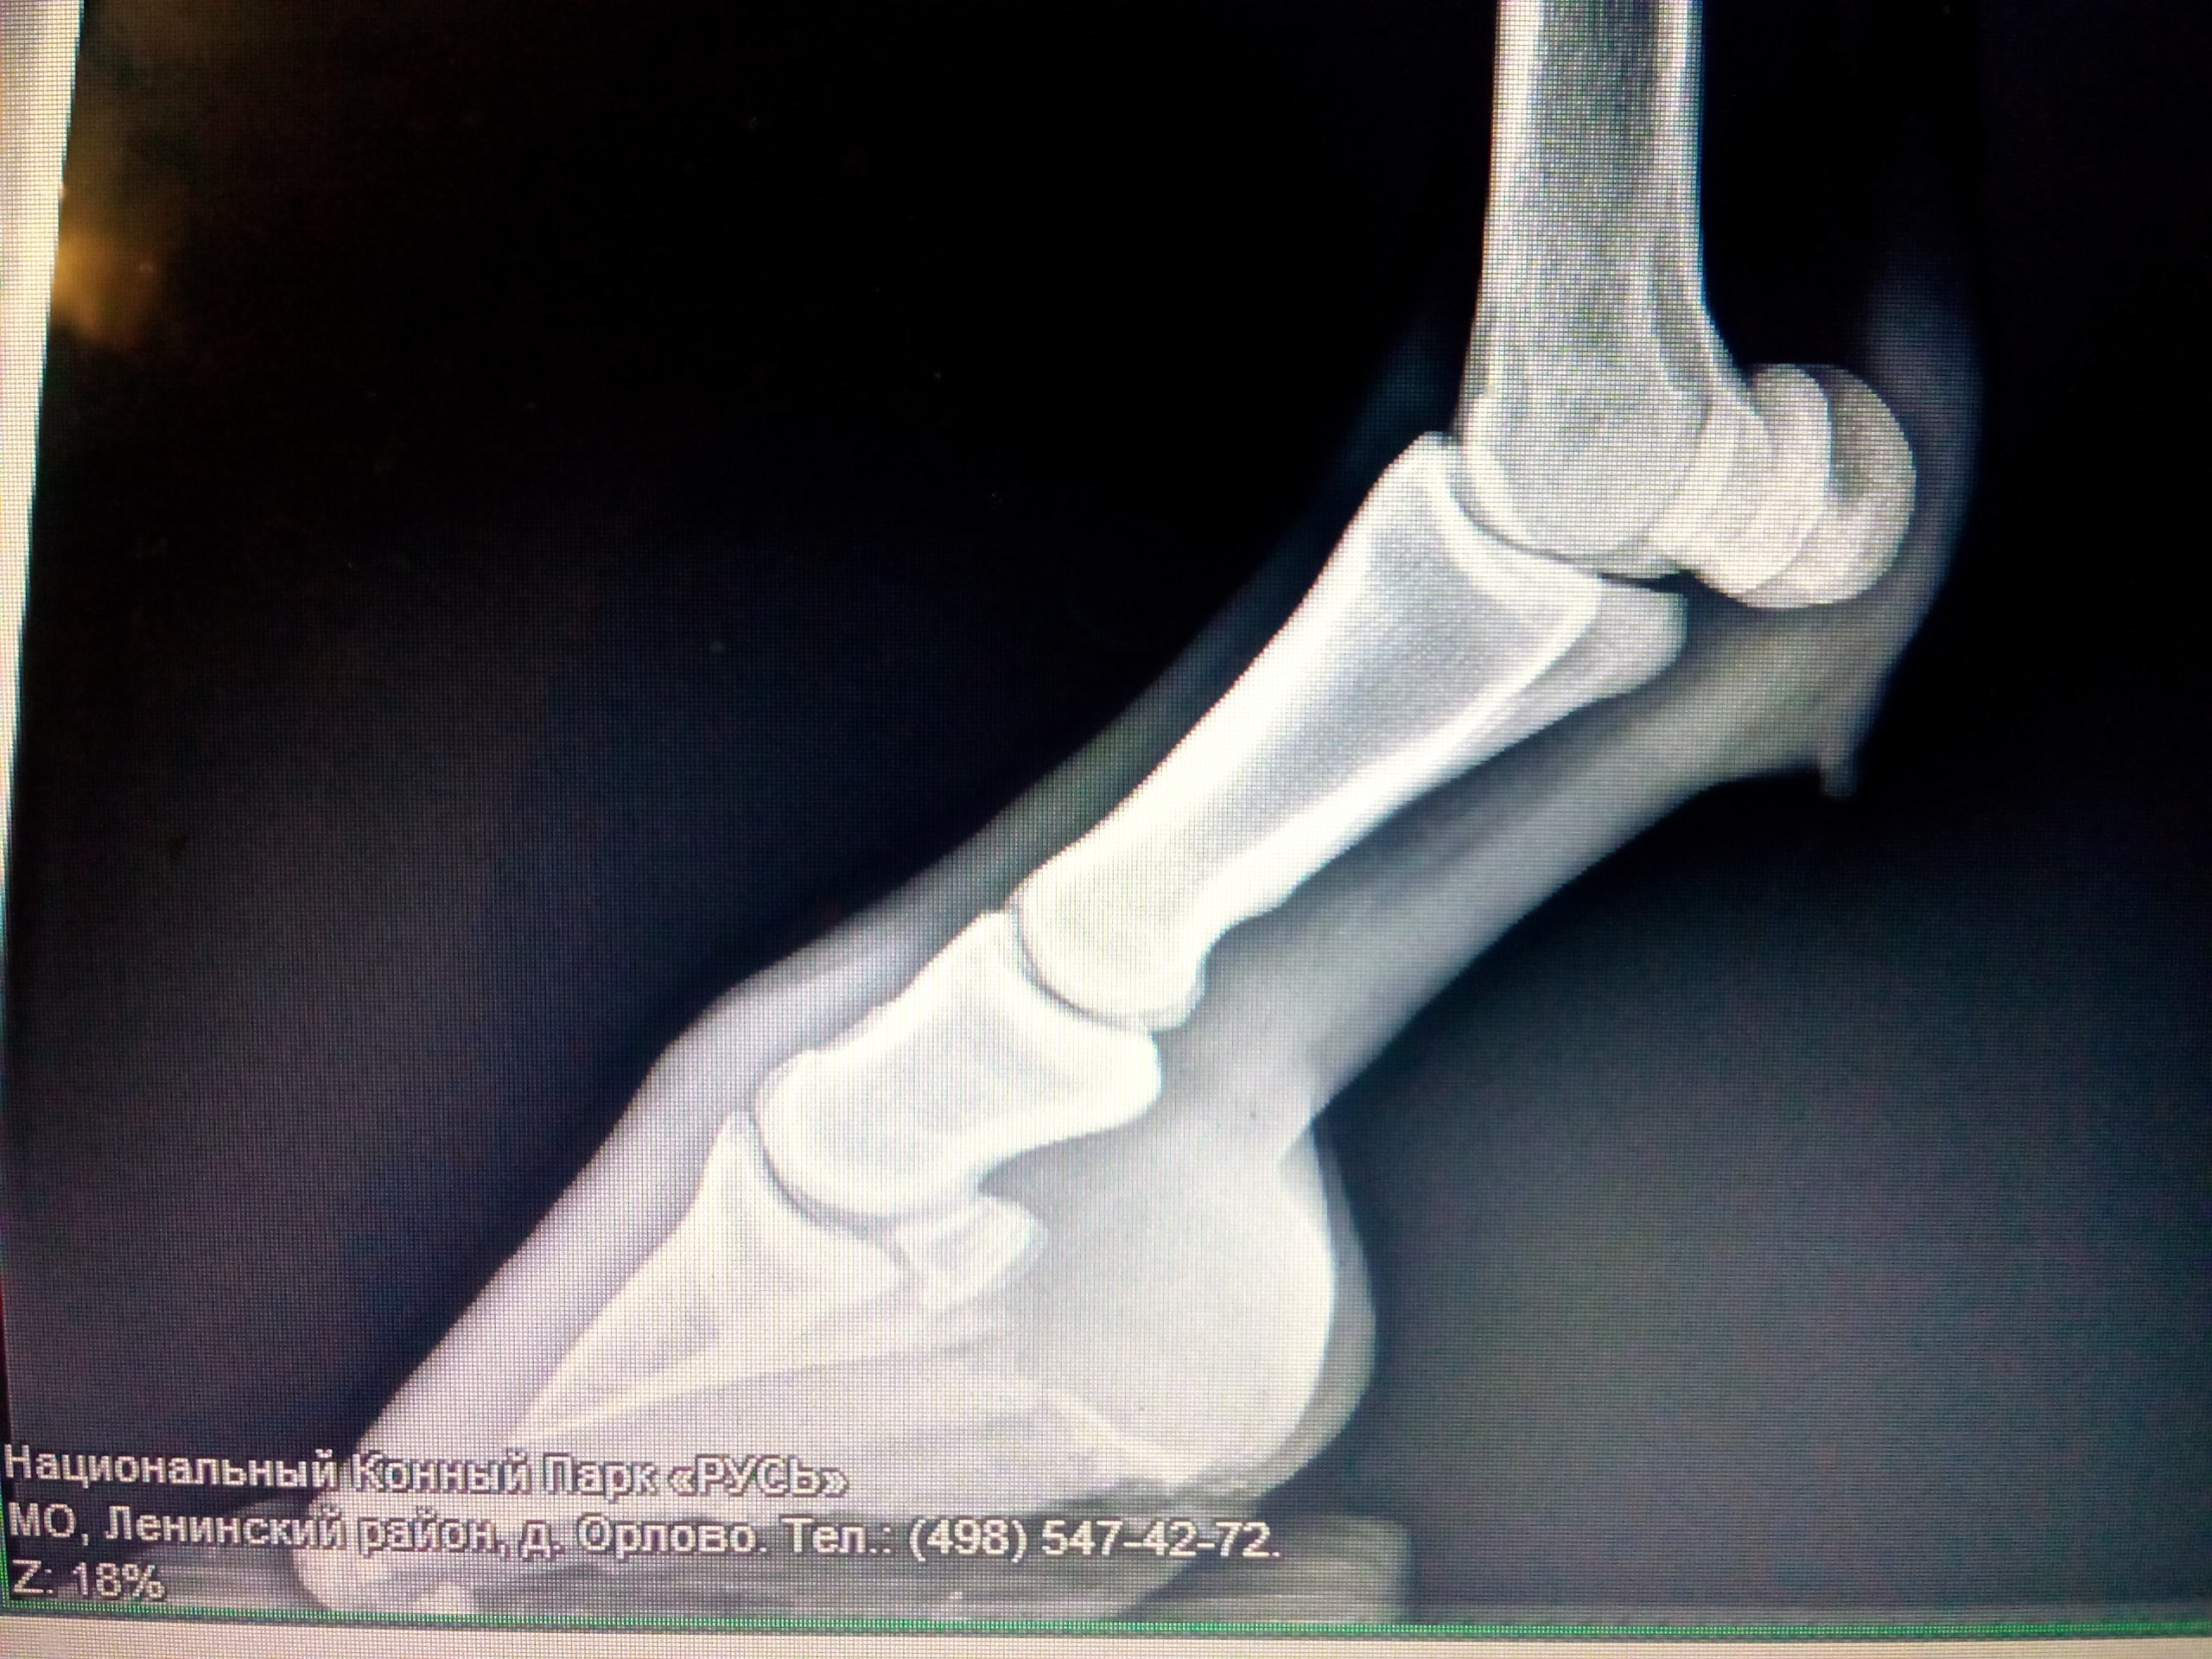

Здравствуйте.история уже долгая..в мае уехала в отпуск.конь неделю работался другим человеком.Вернулась ,вывела коня на тренировку на корду.Показалось конь припадает на ПЛ .На след.день взяла под верх.Шагал нормально,а на рыси начал костылять.Весь сдался и двигаться вперёд отказывается.Конь был осмотрен ветом, ничего не обнаружено.В последующие дни ситуация не изменилась.Опрос человека который работал коня ничего не дал.По словам все было нормально.Сначала думали плечо-мазали ,растирали.Безрезультатно.Прокололи Флексопрофен.Травматин курсом.Ничего не изменилось.Все это время конь шагался.Через два месяца шагания ситуация не изменилась.Конь по прежнему хромал на рыси.Глаз мой настолько уже замылился,что мне казалось конь весь кривой..У нас в городе нет конной диагностики.4 месяца ждали врача с рентгеном из Москвы.Врач приехала только 9 октября.Сделали рентген,конь был ощупан весь.Сказала спина ,плечи в порядке.Хромота наступательная и нужна ортопедическая ковка.В рентгене при этом ничего не видно.Врач сказала шагать ещё.Вот мы все шагаем.При этом ассиметрия выражена только на рыси.Верхом мы не работаем.Садились только раз в июле,снимали видео движений.В общем вот такая ситуация.Будем рады любой помощи.!видео незнаю как загрузить..